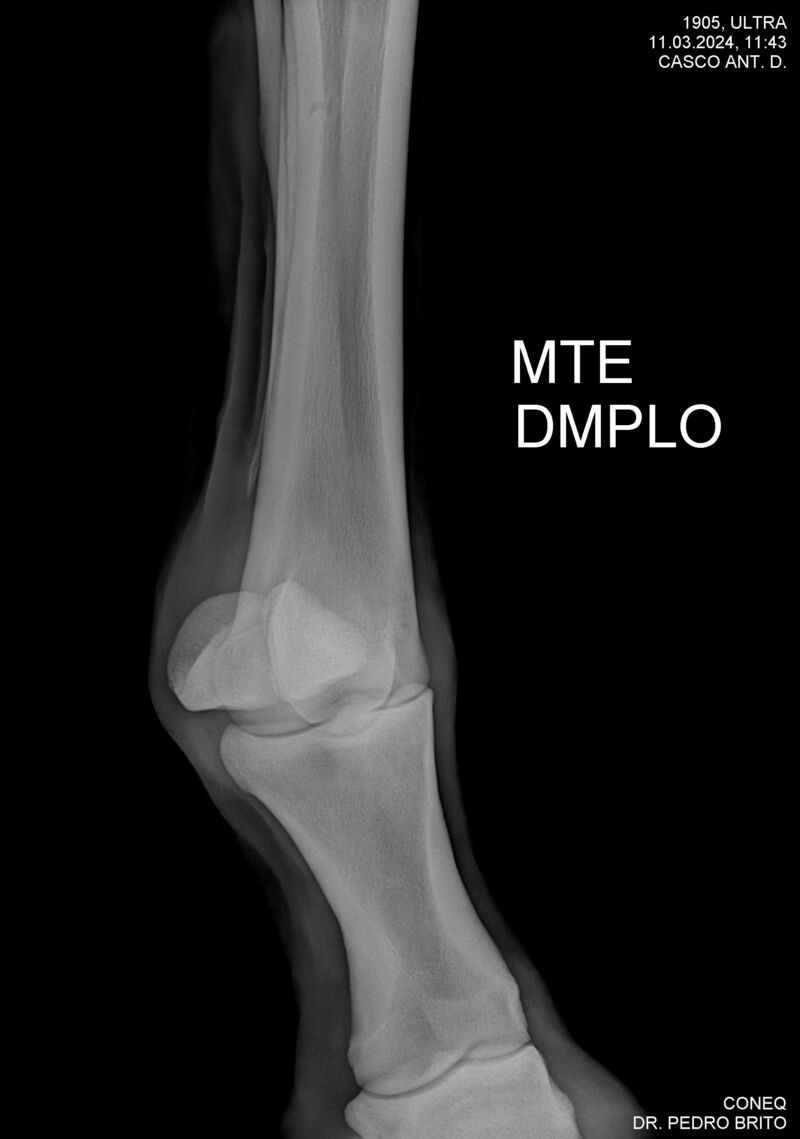

ULTRA DO CACH